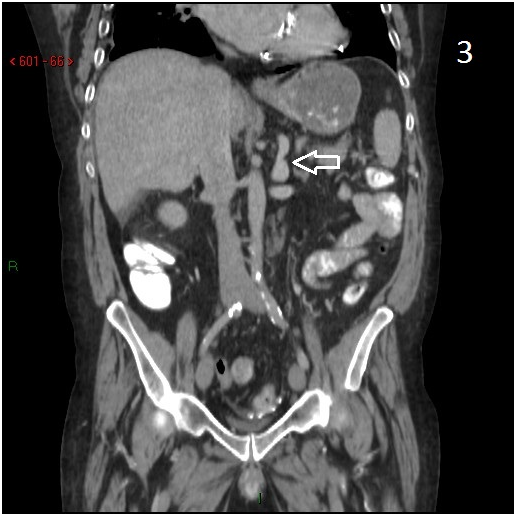

A fifty four years old male presented with intermittent upper gastrointestinal (GI) bleeding. His past medical history was significant for severe heart failure, coronary artery bypass surgery, mechanical aortic and mitral valve replacement, chronic atrial fibrillation, end stage renal failure on hemodialysis, and pacemaker implantation. He had no past history of liver disease, and his liver viral serology was negative. The patient was passing dark stool, and required daily blood transfusions and withdrawal of anticoagulation upon initial stabilization. Upper gastrointestinal endoscopy showed varices at the cardiac portion of the stomach with stigmata of recent bleeding. Due to anatomic location of the varices in the cardia, endoscopic band ligation was not technically possible. Abdominal CT scan showed varices in the vicinity of gastric fundus with spontaneous collateral venous shunt connecting left renal vein and stomach (Figures 1-3).

Figure 2 CT scan, coronary view. There is a spontaneous venous shunt (arrow), taking off the left renal vein.

Figure 3 Additional coronary CT view, showing the direction of the shunt towards the stomach.